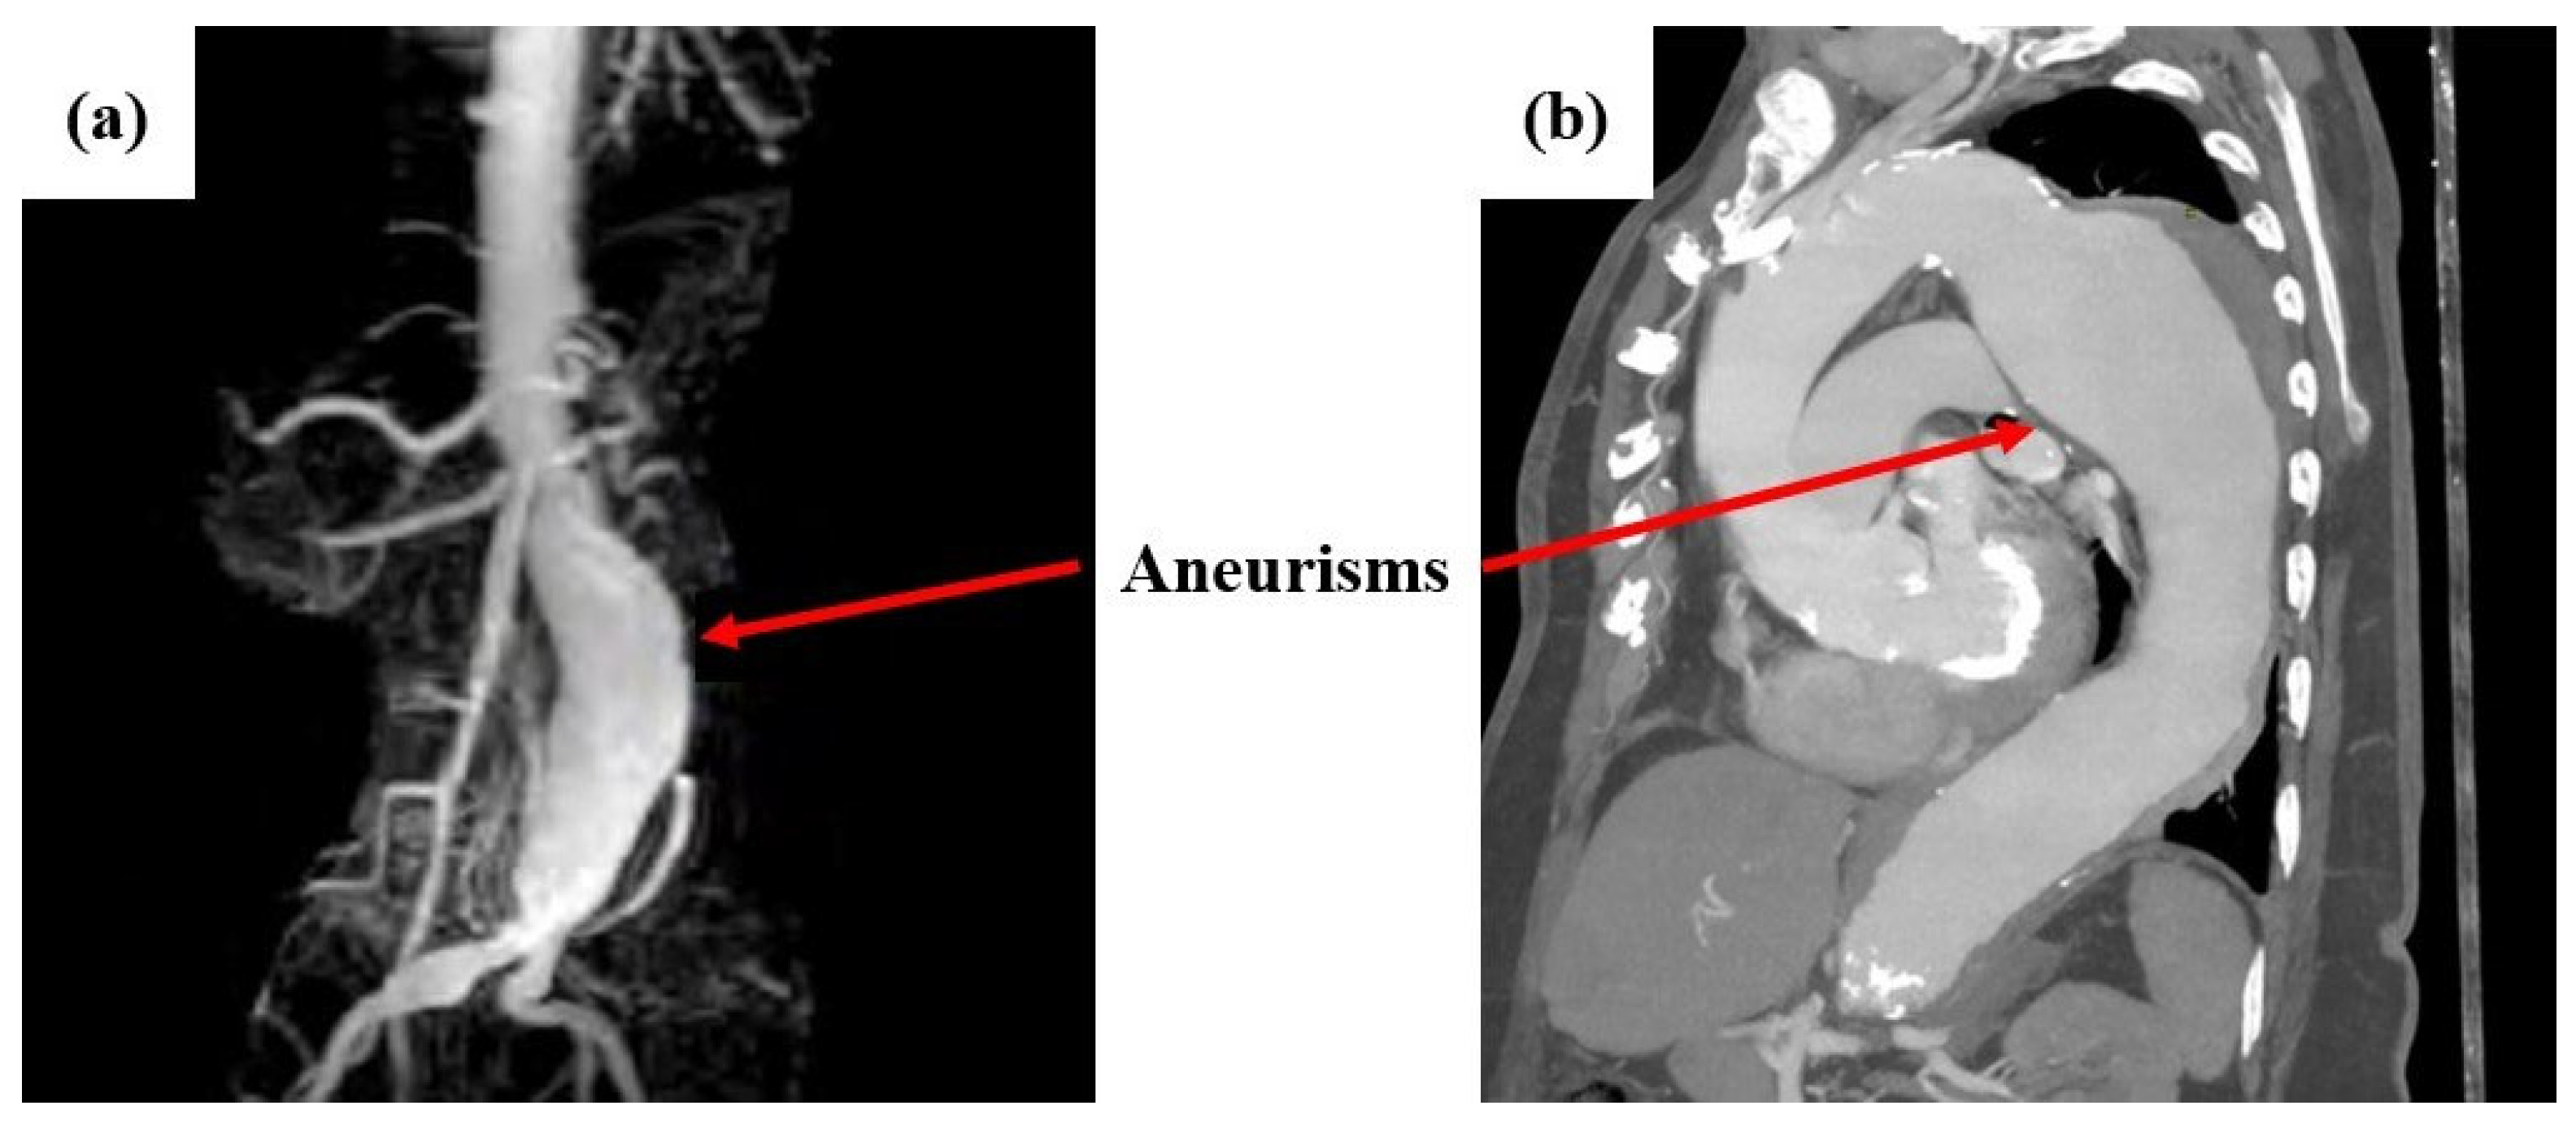

The causes of aneurysms are not predetermined, but factors such as heredity, atherosclerosis, diabetes, hypertension, or injuries from previous vascular surgery may contribute to their occurrence [6]. Usually, patients do not show symptoms as aneurysms are often incidental findings during tests. However, some of the most common symptoms include abdominal, chest, back, or groin pain, as well as palpitations in the abdomen in synchrony with the heartbeat. In rare cases, areas of blue color and pain may appear in the feet and toes due to the dispersal of debris from the aneurysm downward [7]. Aneurysms are usually diagnosed as incidental findings because patients are asymptomatic. They are typically detected through, computed tomography (CT) or angiography (CTA), triplex ultrasound, magnetic resonance imaging (MRI), or angiography (MRA). In very rare cases, when imaging tests are negative, but an aneurysm is strongly suspected, more specialized tests may be necessary (Positron Emission Tomography (PET) Scan, etc.) [8]. Indicatively, Figure 1 shows cases of abdominal aortic aneurysms captured with MRA (left) and MRI (right) imaging [9,10].

Figure 1. Indicative images of abdominal aortic aneurysms captured with: (a) MRA and (b) MRI imaging [9,10].